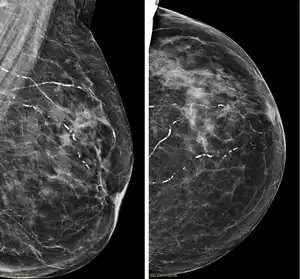

| Right breast mammograms showing several calcified arterioles. Patient 94 years old. | |